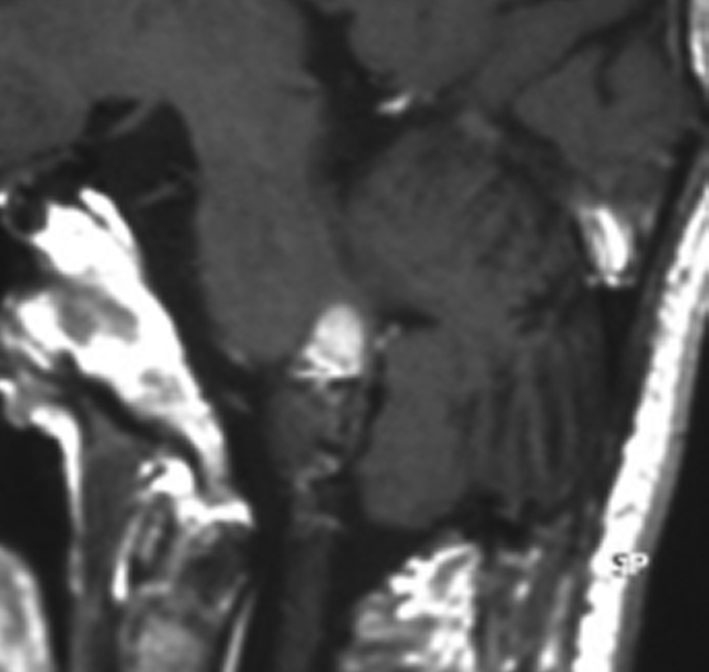

左から,33歳時,35歳時,39歳時の延髄出血です。11歳の時にジャーミノーマで全脳室照射を40グレイ受けました。ジャーミノーマは治ったのですが,延髄左側に海綿状血管腫が22年後に発生して,延髄出血を繰り返しました。もちろん手術などはしません。自然に吸収されてまた落ち着きます。